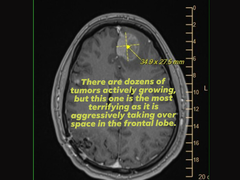

Bizonyítékként csatolt egy képet egy agyi vizsgálatról (MRI) is, amely egy agresszív homloklebenyi daganatot mutatott, miközben támogatásért vagy segítségért könyörgött az Epic Games vezetőihez, akik az elbocsátásokkal kapcsolatos kulcsfontosságú döntéseket hozták.